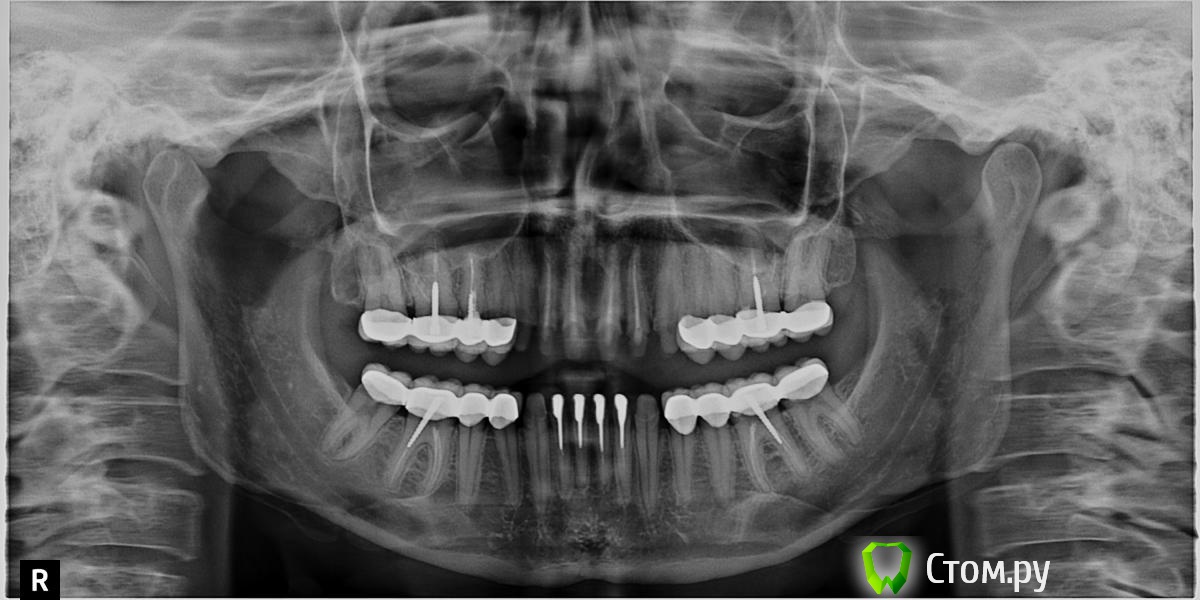

Добрый день! Вопрос по прделанной работе. Оцените,поож-та, качество пломбировки каналов и прилегание коронок , удалены нервы в передних 4 верхних и нижних зубах  - стоят временные коронки. Также удалены и некоторые нервы в боковых зубах - стоят коронки м/к. Врач ,который проводил работу утверждает что сделано все правильно, другие врачи критикуют работу, в том числе и качество пролечивание каналов.